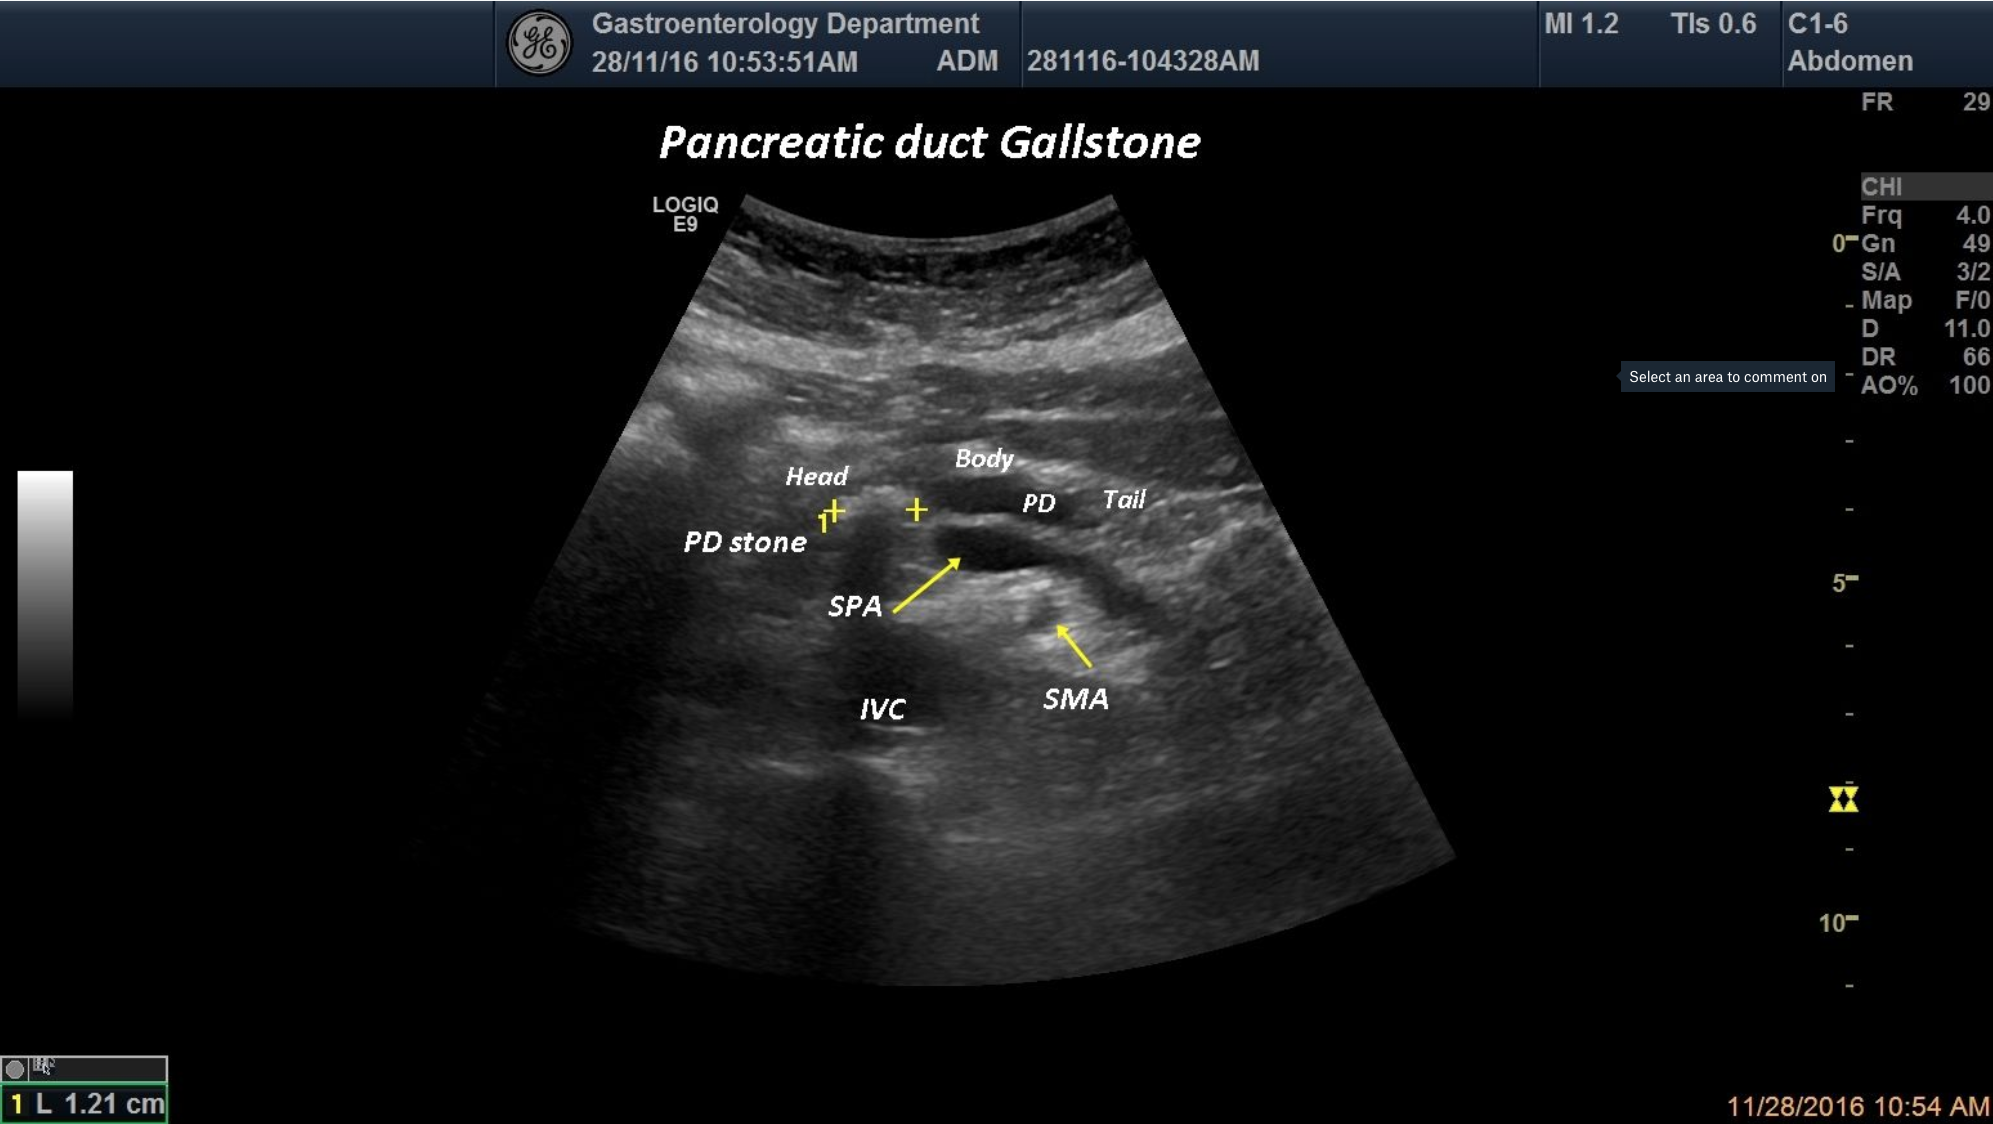

TITLE: Acute on Chronic Pancreatitis, Gallstone inside the Pancreatic Duct

A 57-year-old patient with history of alcohol intake was admitted in the Gastroenterology department with acute pancreatitis. When ultrasound was performed, we depicted a dilated pancreatic duct with a hyperechoic image inside the PD corresponding to a PD stone.